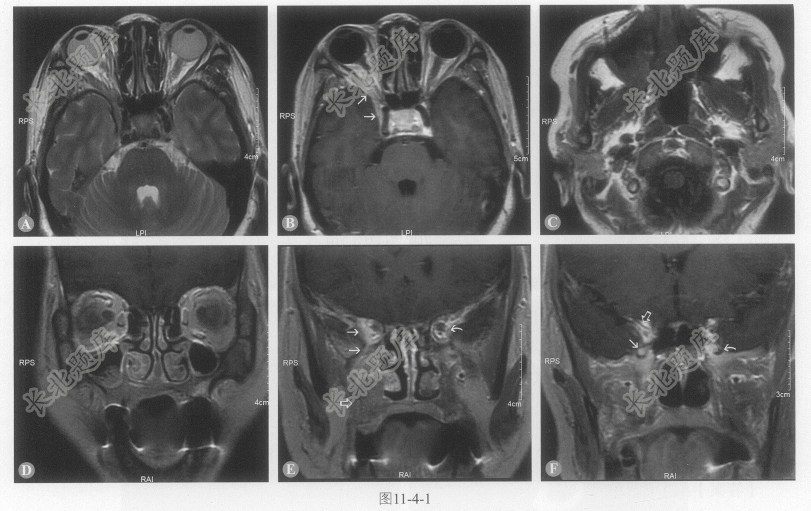

- [材料题] 患者女性,47岁,复视2周。查体,右第Ⅲ、第Ⅴ和第Ⅵ脑神经麻痹,提示眶上裂综合征,影像检查如图11-4-1。

- 多项选择题1.右眶上裂病变(图11-4-1A、B细箭),导致第Ⅲ、第Ⅴ和第Ⅵ脑神经麻痹,该例可能的诊断是:

- 多项选择题3.图11-4-1F细箭所指是:

- 多项选择题4.图11-4-1B和图11-4-1E细箭提示肿瘤: